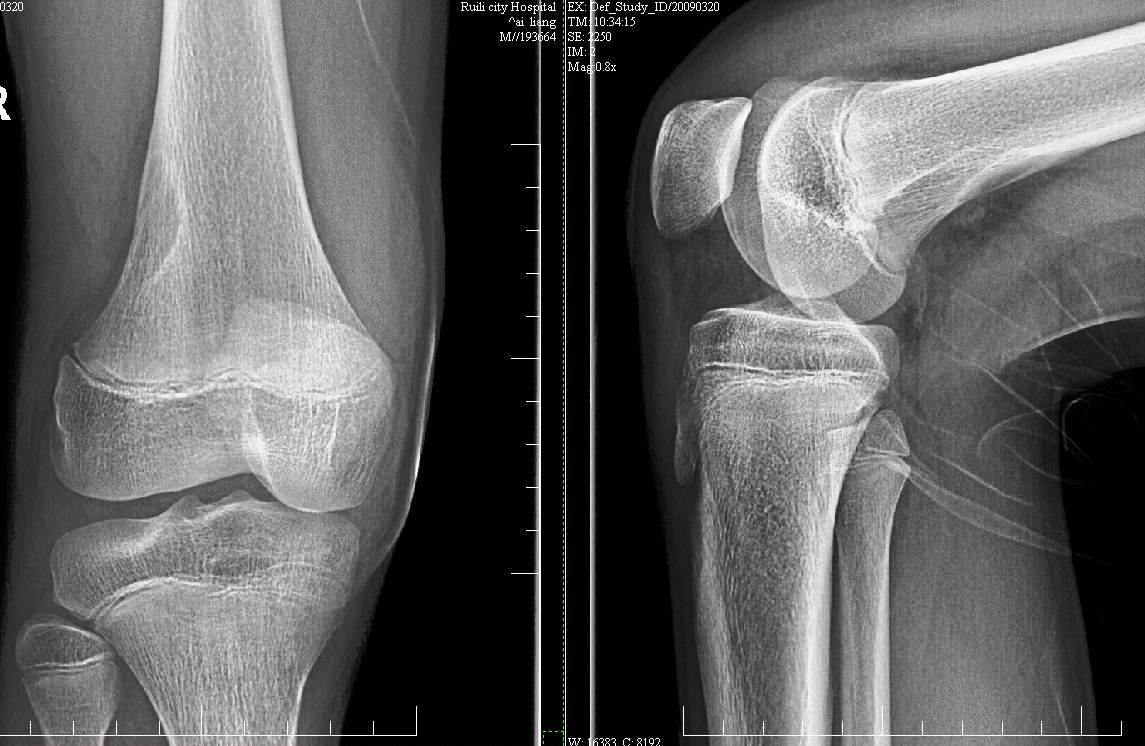

x光:右股骨下段外侧骨质病变,骨囊肿?

ct:右侧股骨下段后份局限性骨质破坏并病灶区细点状高密度影,性质?骨tb可能性大,软骨瘤、纤维骨皮质缺损及其它待除外,建议结合临床及相关检查考虑。 2、右膝关节腔少量积液。